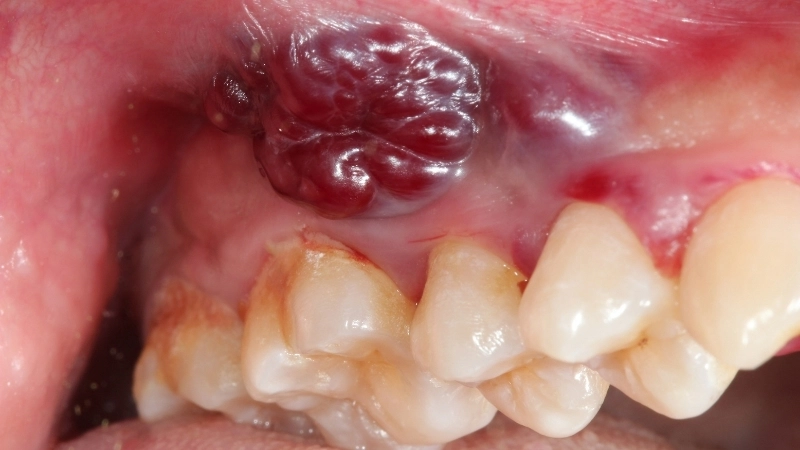

Hình ảnh tổn thương hồng sản, nguy cơ cao của ung thư

• Sự xuất hiện của các đốm đỏ xen kẽ (hồng sản), bề mặt sần sùi hoặc loét là dấu hiệu cảnh báo nguy cơ cao về mối liên hệ giữa bạch sản và ung thư.